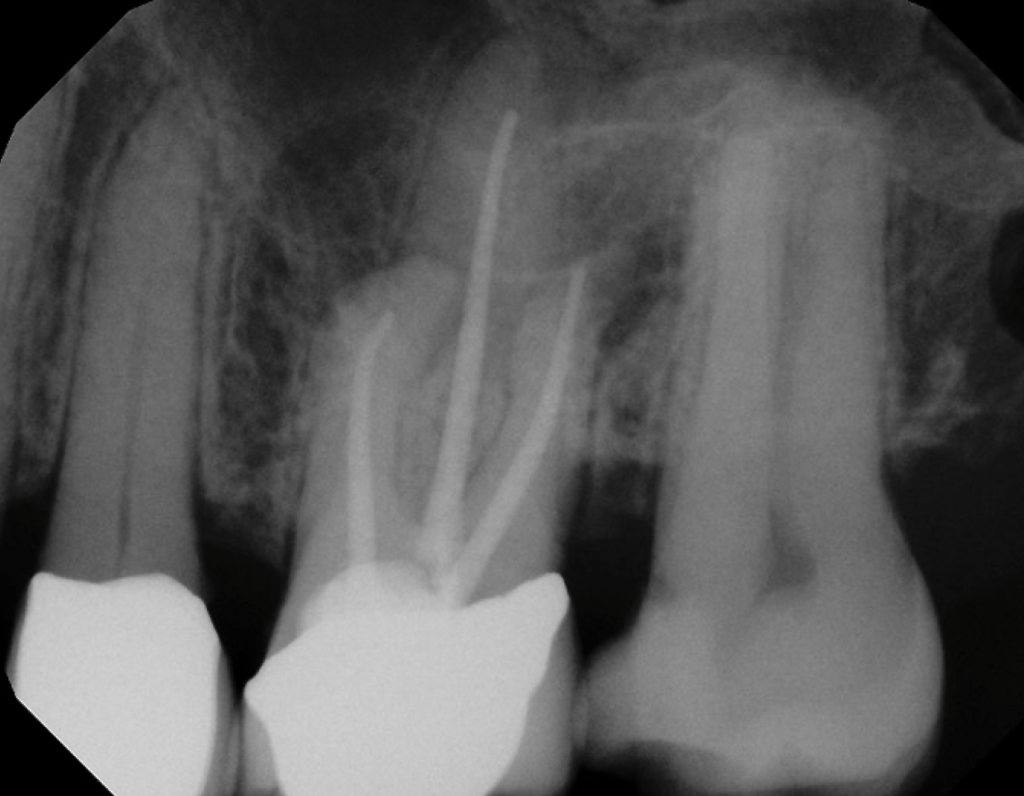

#9 S-RCT

Dx: Previously Treated with SAP

#14 MB root amp with GTR

Dx: Previously Treated with CAA